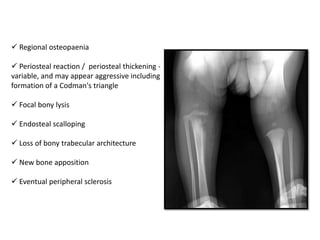

 Regional osteopaenia

 Periosteal reaction / periosteal thickening -

variable, and may appear aggressive including

formation of a Codman's triangle

 Focal bony lysis

 Endosteal scalloping

 Loss of bony trabecular architecture

 New bone apposition

 Eventual peripheral sclerosis